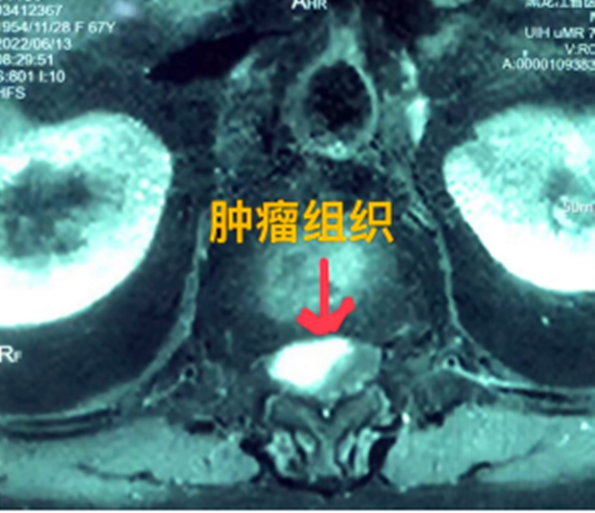

據(jù)省醫(yī)院神經(jīng)外一科陶宇醫(yī)生介紹,家住外地的張大娘最近總感覺(jué)雙下肢疼痛、無(wú)力,且排尿困難及便秘,伴有行走困難。時(shí)間長(zhǎng)了,張大娘病情逐漸加重,劇烈的疼痛甚至讓她無(wú)法完整入睡。在當(dāng)?shù)蒯t(yī)院,張大娘按腰椎肩盤突出接受治療,但未見(jiàn)好轉(zhuǎn),隨后進(jìn)行的胸椎MRI(核磁共振)檢查,結(jié)果不禁讓張大娘和家屬瞠目結(jié)舌,原來(lái)張大娘患的竟然是少見(jiàn)的脊髓腫瘤。

張大娘住進(jìn)了黑龍江省醫(yī)院神經(jīng)外一科,該科孫國(guó)章主任醫(yī)師熱情地接待了張大娘,并邀請(qǐng)骨外一科專家共同為她進(jìn)行了聯(lián)合會(huì)診。發(fā)現(xiàn)張大娘病情十分復(fù)雜棘手,脊髓腫瘤體積較大,充滿髓腔且神經(jīng)已經(jīng)完全受壓,需要手術(shù)來(lái)完整切除。同時(shí)還發(fā)現(xiàn)張大娘的胸腰部曾受過(guò)兩次外傷,伴有多處骨折,這對(duì)接下來(lái)的手術(shù)操作帶來(lái)一定影響。